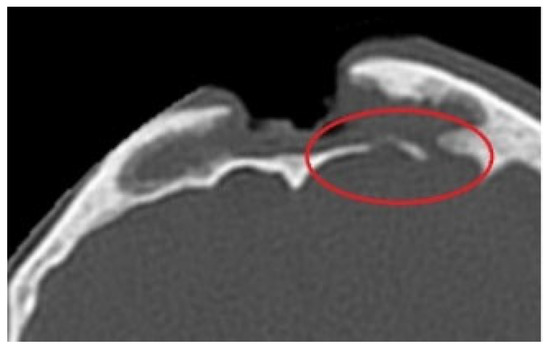

Another medical case meeting was held, this time with specialists in neurosurgery and maxillofacial surgery. Frontal sinus obliteration was planned: however, a defect was noted in the posterior wall of the frontal sinus (Figure 7) together with a 10 mm-wide fluid space in the temporoparietal region (Figure 8) with a density of 15 Hounsfield units, a dilated Sylvian fissure. Therefore frontal sinus cranialization was eventually proposed.

Figure 7. Defect in the posterior wall of the frontal sinus, CT scan.

Figure 8. Fluid space in the frontotemporal region, CT scan.